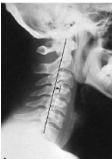

Q what is the name of this measurement? and what is the average + range?

A: Posterior Cervical Line

assesses for a smooth, arc-like curve of the spinolaminar junctions. No average or range is specified, but significance in children notes the C2 junction should not be more than 2 mm anterior to the line.